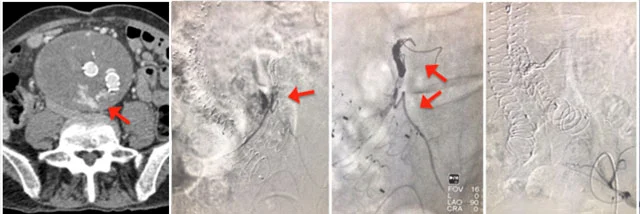

Guida radiologica durante embolizzazione per endoleak di tipo III da disconnessione della protesi

EL Tipo III